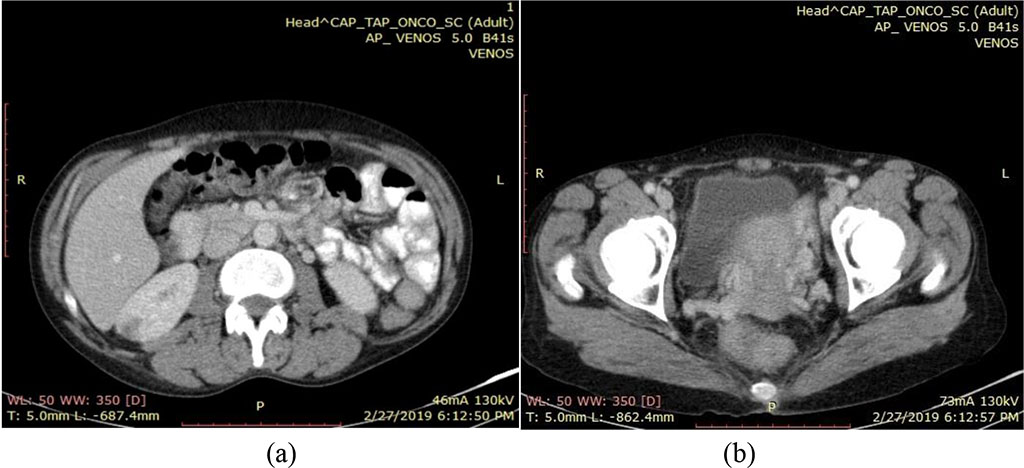

After pretherapy evaluation, the multidisciplinary committee decides on concomitant radio-chemotherapy treatment, along with brachytherapy. It is well tolerated by the patient, with no digestive or hematological toxicity. During the second week of treatment, clinical examination revealed left cervical and supraclavicular adenopathy. In this case the patient is evaluated through imaging studies which documented the presence of left cervical and supraclavicular lymph node enlargement, of a right renal, poorly iodophilic, heterogeneous image measuring a diameter of 16,5 mm (Fig.2), a globular cervix measuring 33 mm (Fig.2), with no retroperitoneal adenopathy and intense disk and bone structure alterations located at the level of the 4th and 5th cervical vertebrae.

Fig.2. CT

scan February 2019 - (a) a right renal, poorly iodophilic,

heterogeneous image, and (b) globular cervix – 33mm.

Source:

Authors' own work